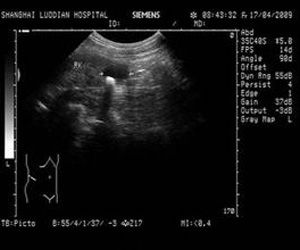

1.B超

顯示腎盞憩室或腎積水的液性暗區,內有圓形回聲光團。